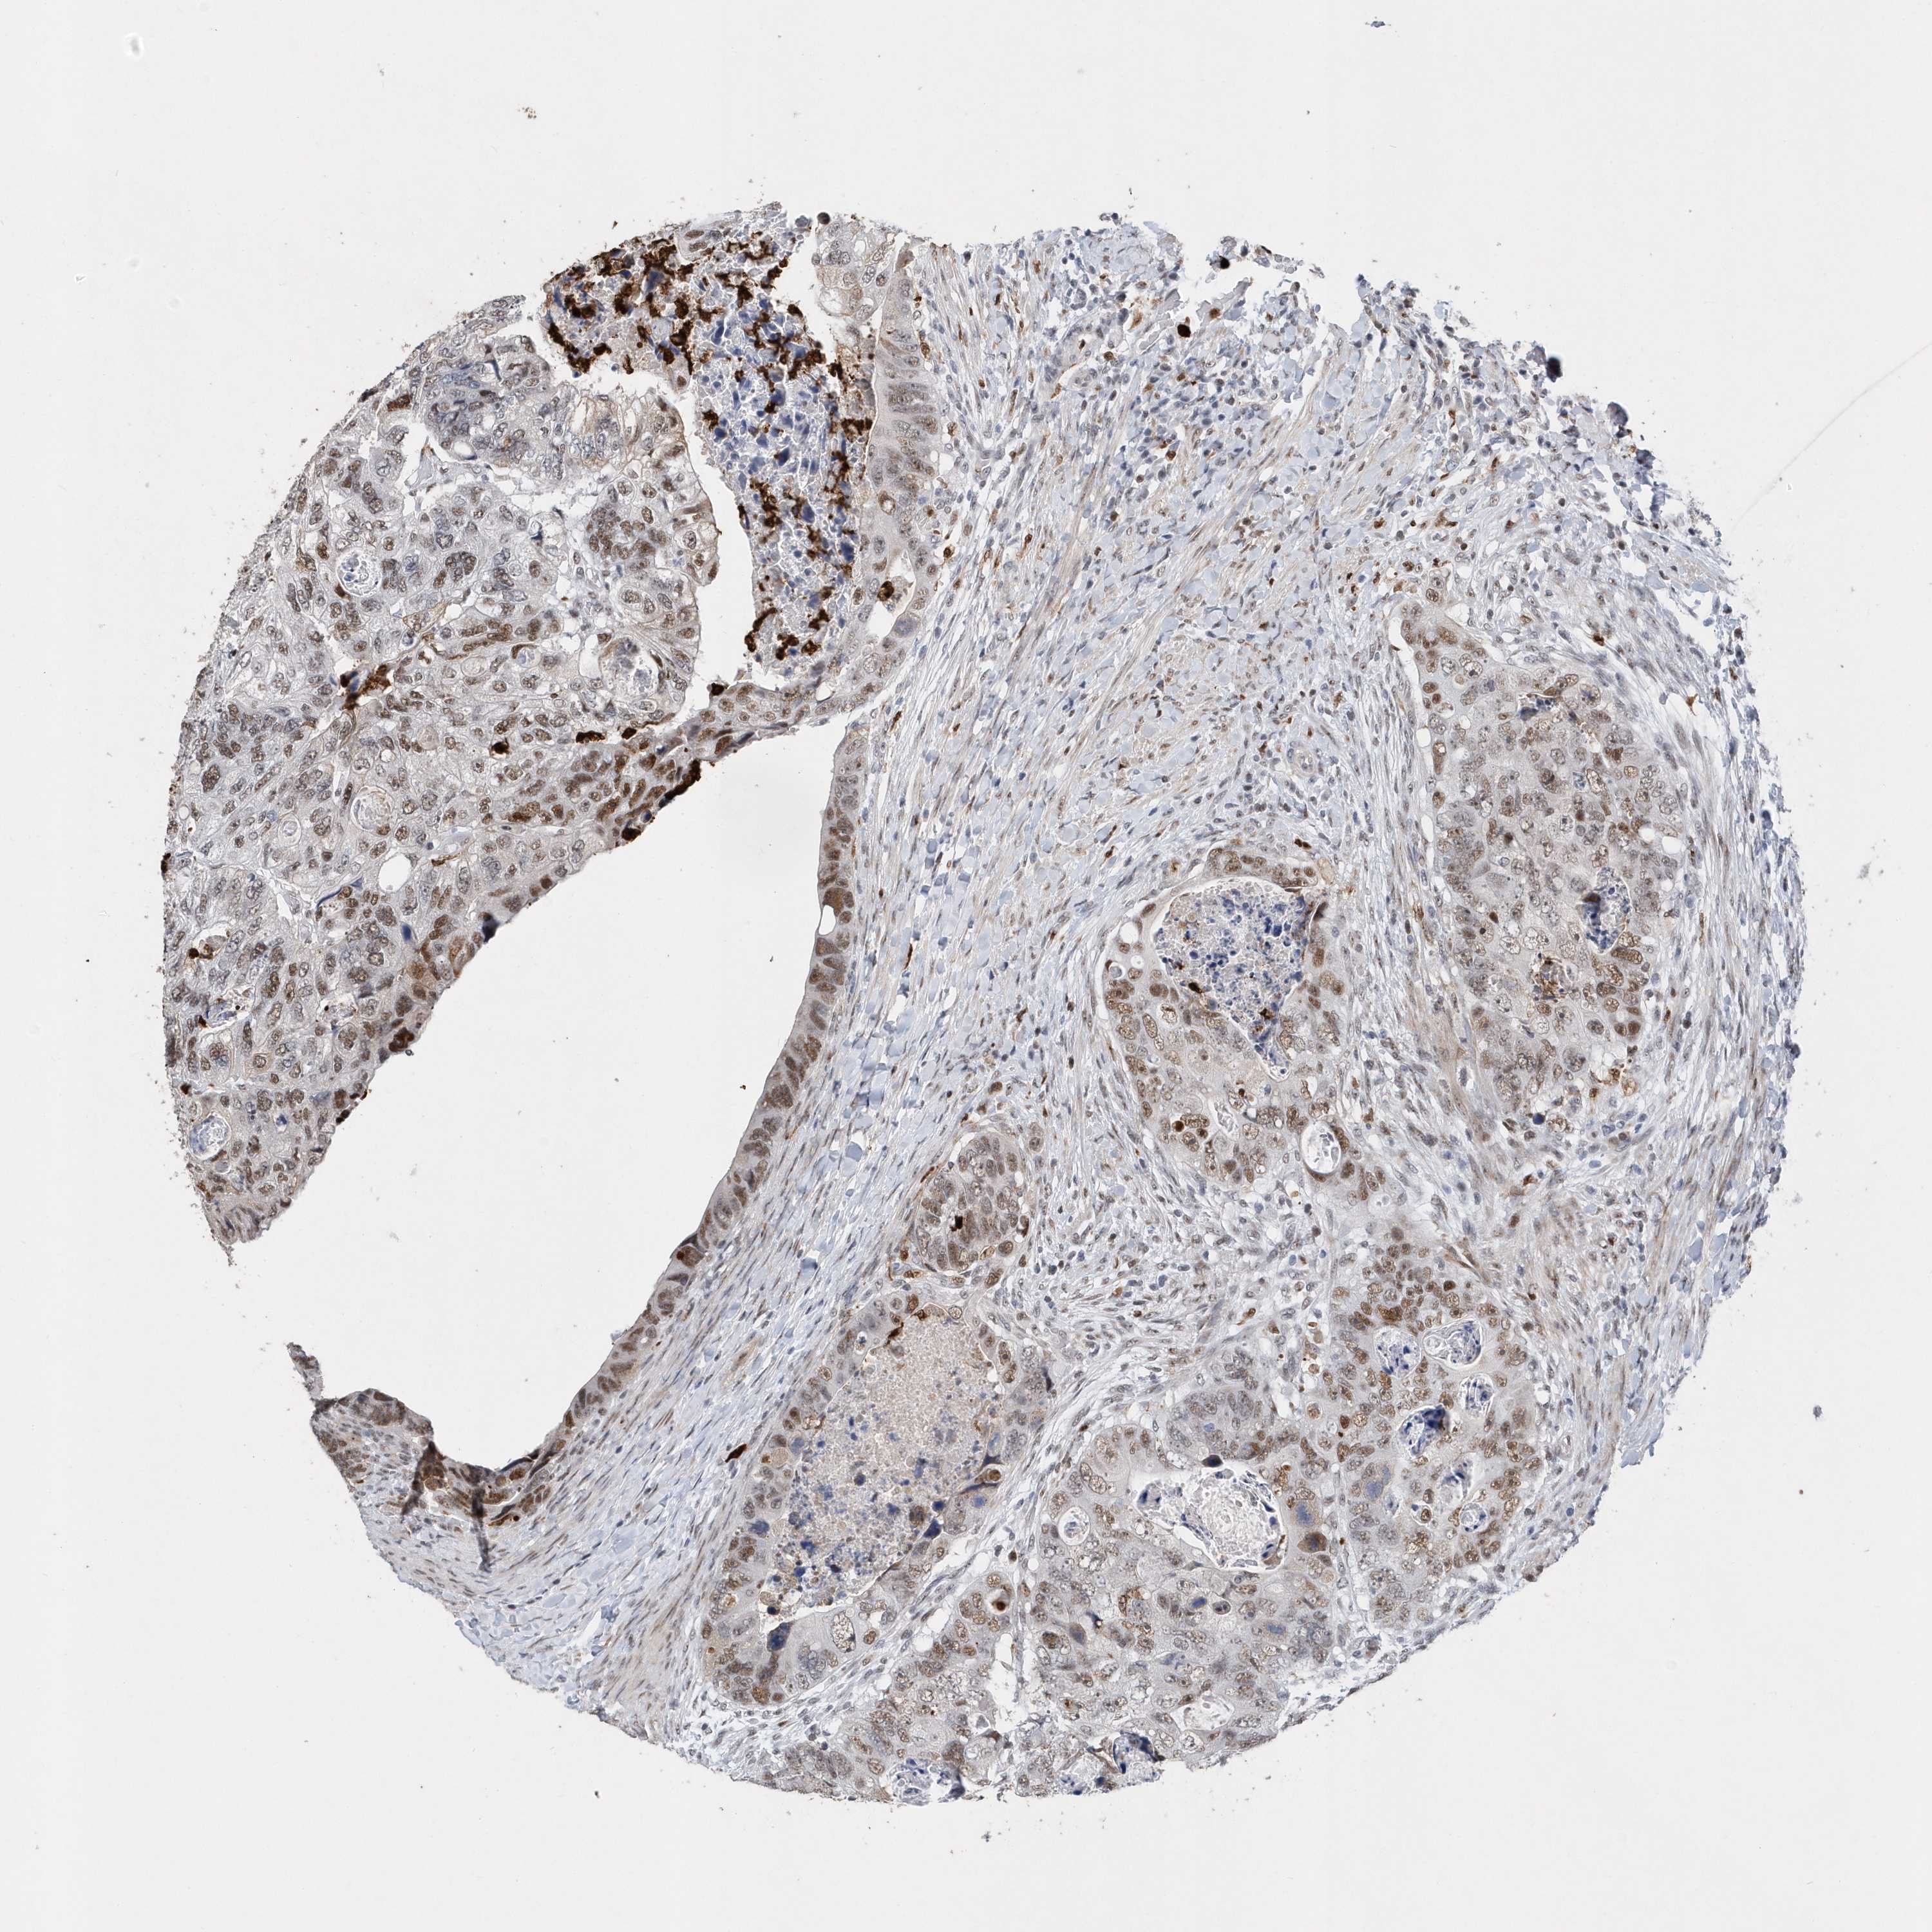

CANCER COLORECTAL CANCER Show tissue menu

Colorectal cancer

Human cancer

Colon adenocarcinoma